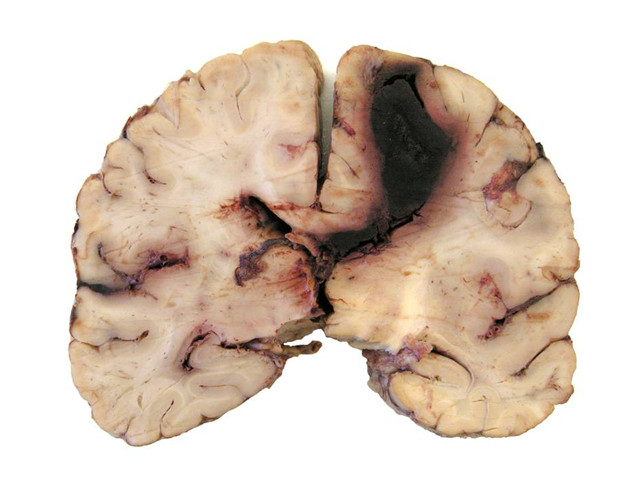

Na przekroju przez półkule mózgu widoczny jest: